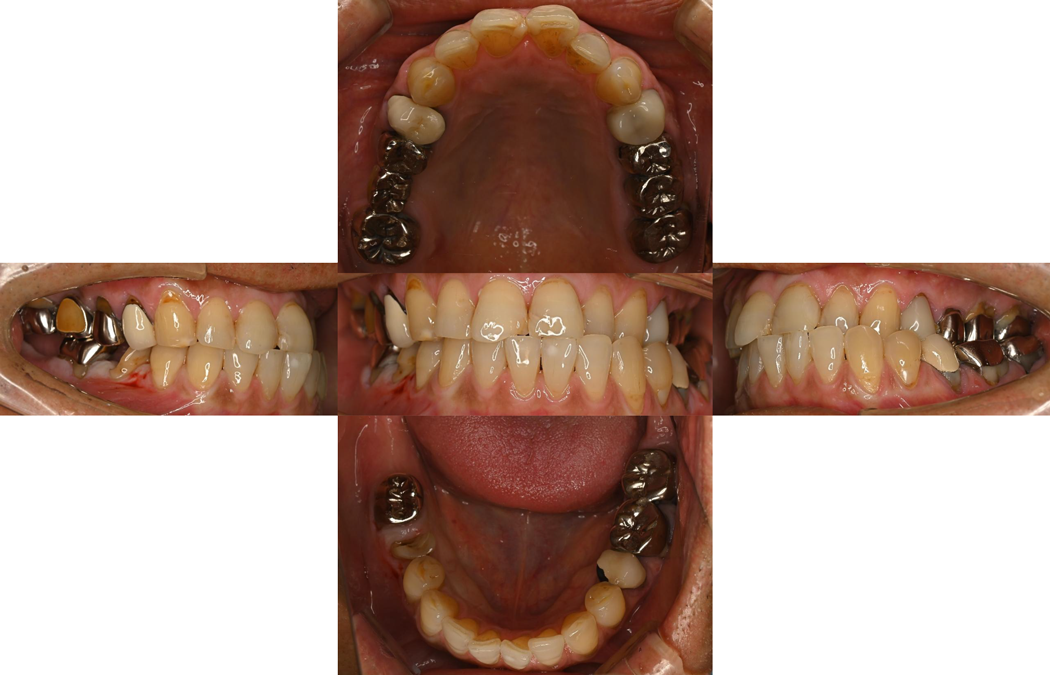

口腔内・画像所見

全顎的に保険診療の治療痕があり、咬合崩壊を起こしている常態でした。前歯部は反対咬合を認め咬合状態の難易度も高い状態でした。

画像所見からは、骨の状態は正常であることがわかりました。

下顎骨の顎角部の凹凸を認め咬合力が高いことが見受けられたたため、咬合の改善が必要だと判断できます。

また、根尖部の透過像を臼歯部に認めたため、治療が必要であることを説明しました。